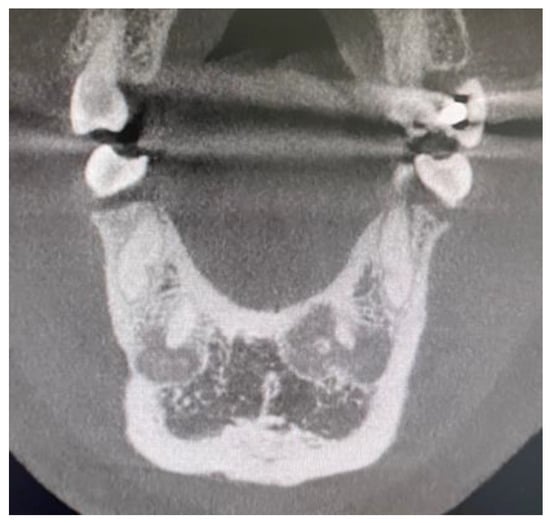

- self-limiting radiolucency, Figure 4

- no changes within the teeth root apex, Figure 3